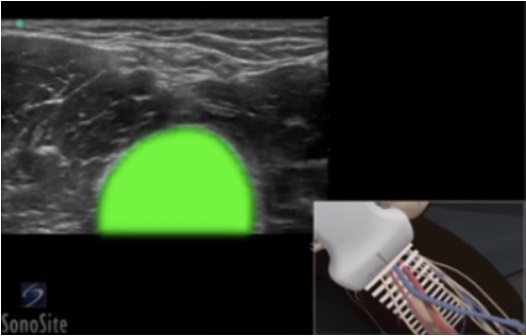

Peripheral IV (PIV) Humerus Image

Highlighted Area: Humerus